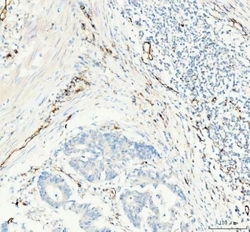

- Submitted by

- NSJ Bioreagents (provider)

- Main image

- Experimental details

- IHC staining of FFPE human glioblastoma tissue with CD31 antibody. HIER: boil tissue sections in pH8 EDTA for 20 min and allow to cool before testing.

- Submitted by

- NSJ Bioreagents (provider)

- Main image

- Experimental details

- IHC staining of FFPE human colorectal adenocarcinoma tissue with CD31 antibody. HIER: boil tissue sections in pH8 EDTA for 20 min and allow to cool before testing.

- Submitted by

- NSJ Bioreagents (provider)

- Main image

- Experimental details

- IHC staining of FFPE human testicular germ cell tumor tissue with CD31 antibody. HIER: boil tissue sections in pH8 EDTA for 20 min and allow to cool before testing.